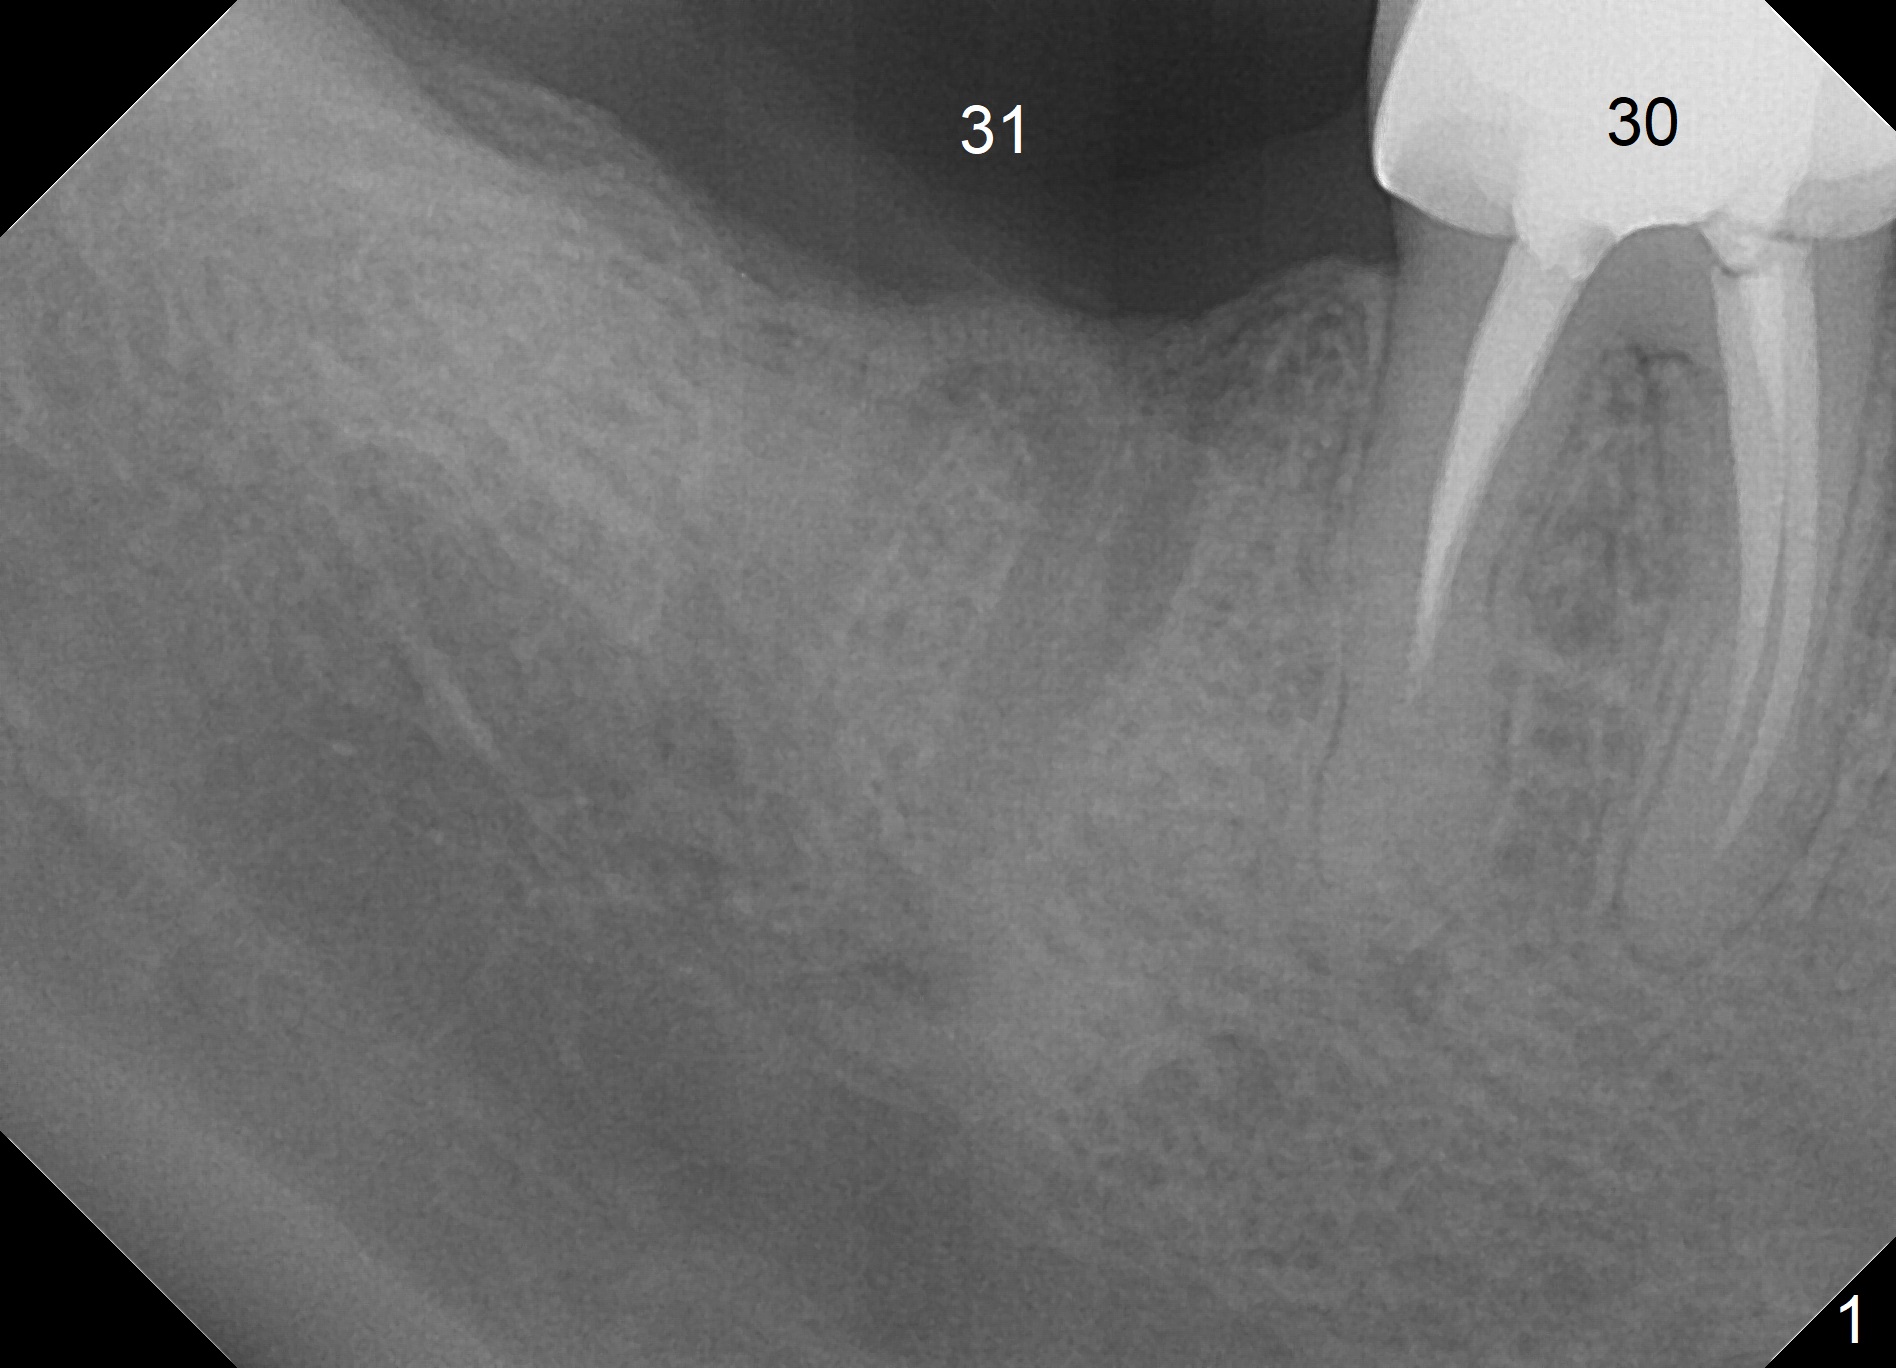

A 47-year-old man requests extraction of the tooth #30 for implant in spite of the fact of missing #31 (Fig.1), The tooth #30 remains symptomatic after RCT retreatment by a specialist. The apical distal canal is obliterated.